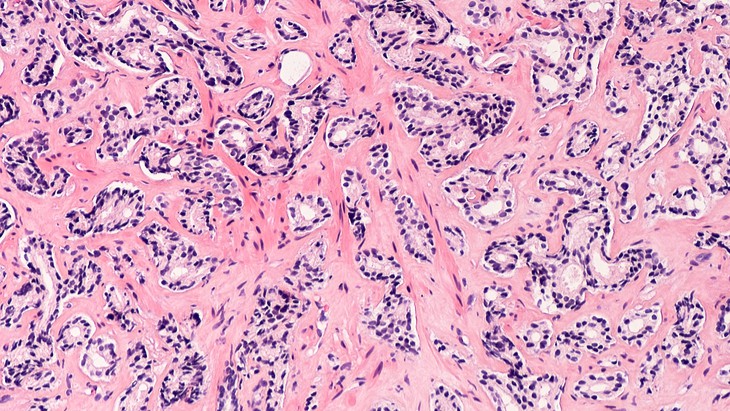

The holy grail in oncology is ‘how do you cure cancer that as spread?’ At the moment, all types of cancer, except a few rare malignancies, cannot be cured after they have spread beyond the original site. Chemotherapy can wipes out vast swathes of cancer cells and keep them at bay, but is usually used […]

How do you cure cancer that has spread?